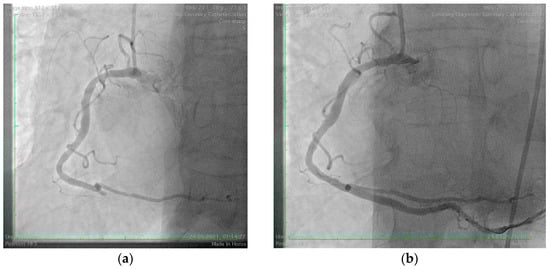

A 75-year-old male, an ex-smoker with multiple cardiovascular risk factors, including grade I obesity, hypertension, and dyslipidemia, was referred to our clinic following a postero-infero-lateral ST-segment elevation myocardial infarction (STEMI) (Figure 1). Symptoms of angina began five hours before presentation and were preceded by a bee sting, which triggered a syncope. The patient was undergoing immunomodulatory therapy for rheumatoid arthritis, including methotrexate, adalimumab, and tamsulosin, and had a history of atopy and anaphylactic shock secondary to a bee sting. On admission, the patient was hemodynamically and respiratory stable, with a blood pressure of 144/75 mmHg, a heart rate of 77 bpm, and oxygen saturation (SpO2) of 99%. Laboratory investigations revealed elevated myocardial enzymes, mild renal impairment (eGFR = 55 mL/min/1.73 m2), and systemic inflammatory markers, including leukocytosis (13,620/mm3) with eosinophilia (9.5%), elevated C-reactive protein (CRP = 17.5 mg/L), and IgE levels (180 UI/mL). Coronary angiography identified an acute thrombotic occlusion of the posterior interventricular artery, with no evidence of other atherosclerotic lesions. The occlusion was successfully treated with coronary angioplasty and the placement of a drug-eluting stent (Figure 2). The patient was initiated on dual antiplatelet therapy (aspirin 75 mg once daily and ticagrelor 90 mg twice daily), high-dose statin therapy (atorvastatin 80 mg once daily), an ACE inhibitor (ramipril 5 mg once daily), and a beta-blocker (bisoprolol 2.5 mg once daily). The patient’s clinical course was favorable, with discharge occurring seven days after admission. At discharge, he had a mildly reduced ejection fraction but experienced no further complications.

Figure 2. Coronary angiography of the right coronary artery. (a) Acute thrombotic closure of posterior interventricular artery; (b) Angiography aspect after revascularization by coronary angioplasty with a drug-eluting stent.